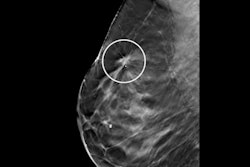

The addition of ABUS helped the reading radiologist to better visualize cancers seen on DBT. With ABUS images, the radiologist correctly upgraded three cases of breast cancer -- two from BI-RADS 4B to 5 and one from BI-RADS 4A to 4B. In addition, ABUS identified invasive lobular carcinoma not seen on DBT.

"In this case, the combined analysis of ABUS and tomosynthesis showed a clear advantage over tomosynthesis alone," the authors wrote. "In the standard diagnostic workup, this carcinoma presented as a palpable lesion with a sonographic correlate in [handheld ultrasound] but no mammographic correlate."